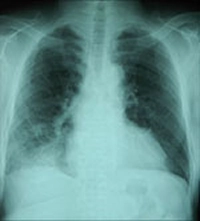

肺炎の胸部X線写真

• 1. 肺炎球菌性肺炎の胸部Xp写真を示します。

• 2. 右肺下葉に浸潤影を認めます。

• 3. 主訴は発熱、全身倦怠感、咳、喀痰です。

肺炎の診断は胸部XP写真が最も迅速で、かつ、有効です。治療や経過の判定には喀痰菌検査、血液検査も必要です。